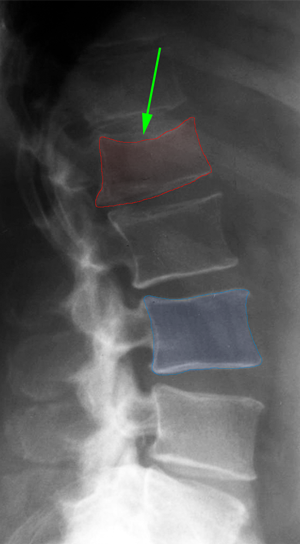

Κάταγμα Ο1 σπονδύλου (κόκκινο) με παραμόρφωση του σχήματός του. |